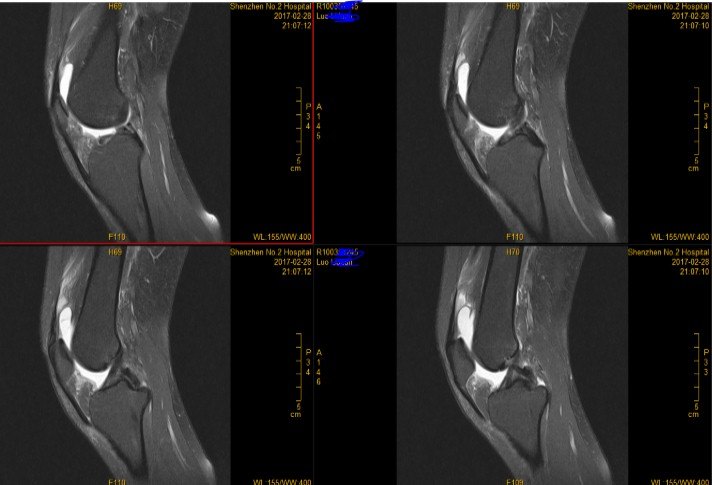

3.MRI(以膝关节为例)

由于MRI和CT一样也 是三维成像,包括矢状面,冠状面和横断面三个层面的扫描。一张MRI片子也是包括医院、姓名、性别、年龄、检查日期、侧别、扫描序列等信息的。不同的示MRI在片子上是信号的高低(CT时密度的高低),也就是说有T1和T2序列(T2序列表现为关节积液是高信号-发白;T1序列表现为关节积液为低信号—发黑或发灰)。因此MRI上不仅有矢状面、横断面和冠状面,还有T1序列和T2序列。

一般来说T2序列更能反应损伤情况,所以平时观察T2序列的图像要更仔细。T1序列主要观察解剖结构,有些医院一般不常规做。

T2序列矢状面:

T2序列冠状面

T2序列横断面